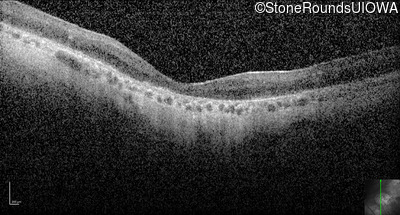

Optical Coherence Tomography - Right - 1/400 sc

Exemplar / OCT Stack